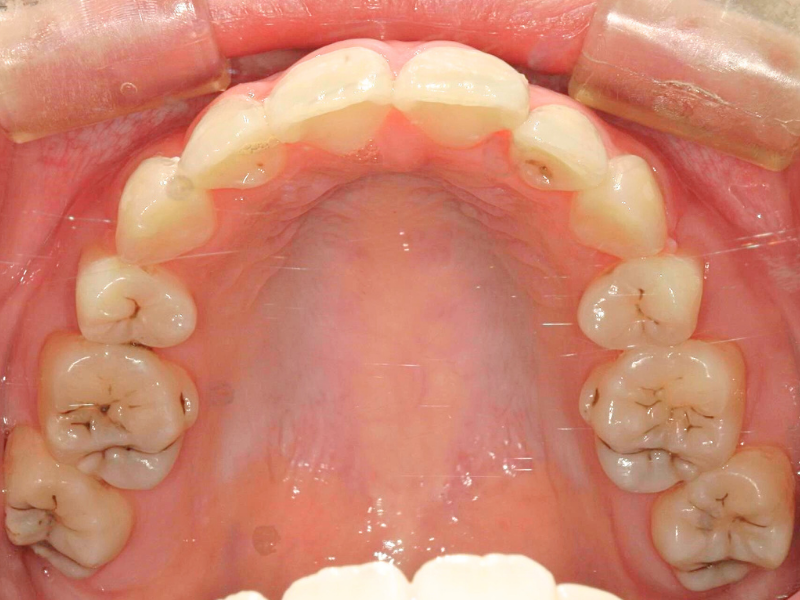

10代、女性、ワイヤー

| 施術内容 | 主訴:上下前歯でこぼこ。なるべく抜きたくない。 詳細:ワイヤー矯正での歯並び改善 詳細:ワイヤー矯正での歯並び改善 歯肉炎リスクあるため、今後は後戻りのチェックとともに歯肉炎管理もしていきます。 |

|---|---|

| 治療期間 | 12ヶ月(2/6現在 治療終了) |

| リスク・副作用 | ■リスク・副作用 ・治療の初期段階では、痛みや不快感が生じやすくなりますが、一週間前後で慣れます。 ・歯の動き方には個人差があるため、予想された治療期間より延長する場合があります。 |

| 費用 | ワイヤー矯正 60万円(税込660,000円) |